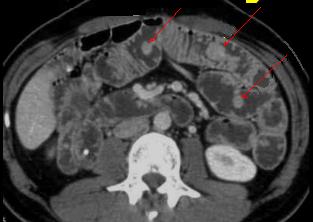

Image TDM en coupe axilal des polyps

hamartomateux de intestin grele . Aspect arrondie ou

ovalaire a bord lisse homogene et hyper-dense se presente

multiple au long de l'intestin et colon ( fleche

rouge ) |

Une autre cas de maladie de Peutz -Jeghers

. Polype multiple de l'intestin avec image des

tumeurs arrondies pedicules a hyper - densite et endo-luminale le long

de l'intestin ( fleche rouge) . Image TDM en coupe

axiale . |